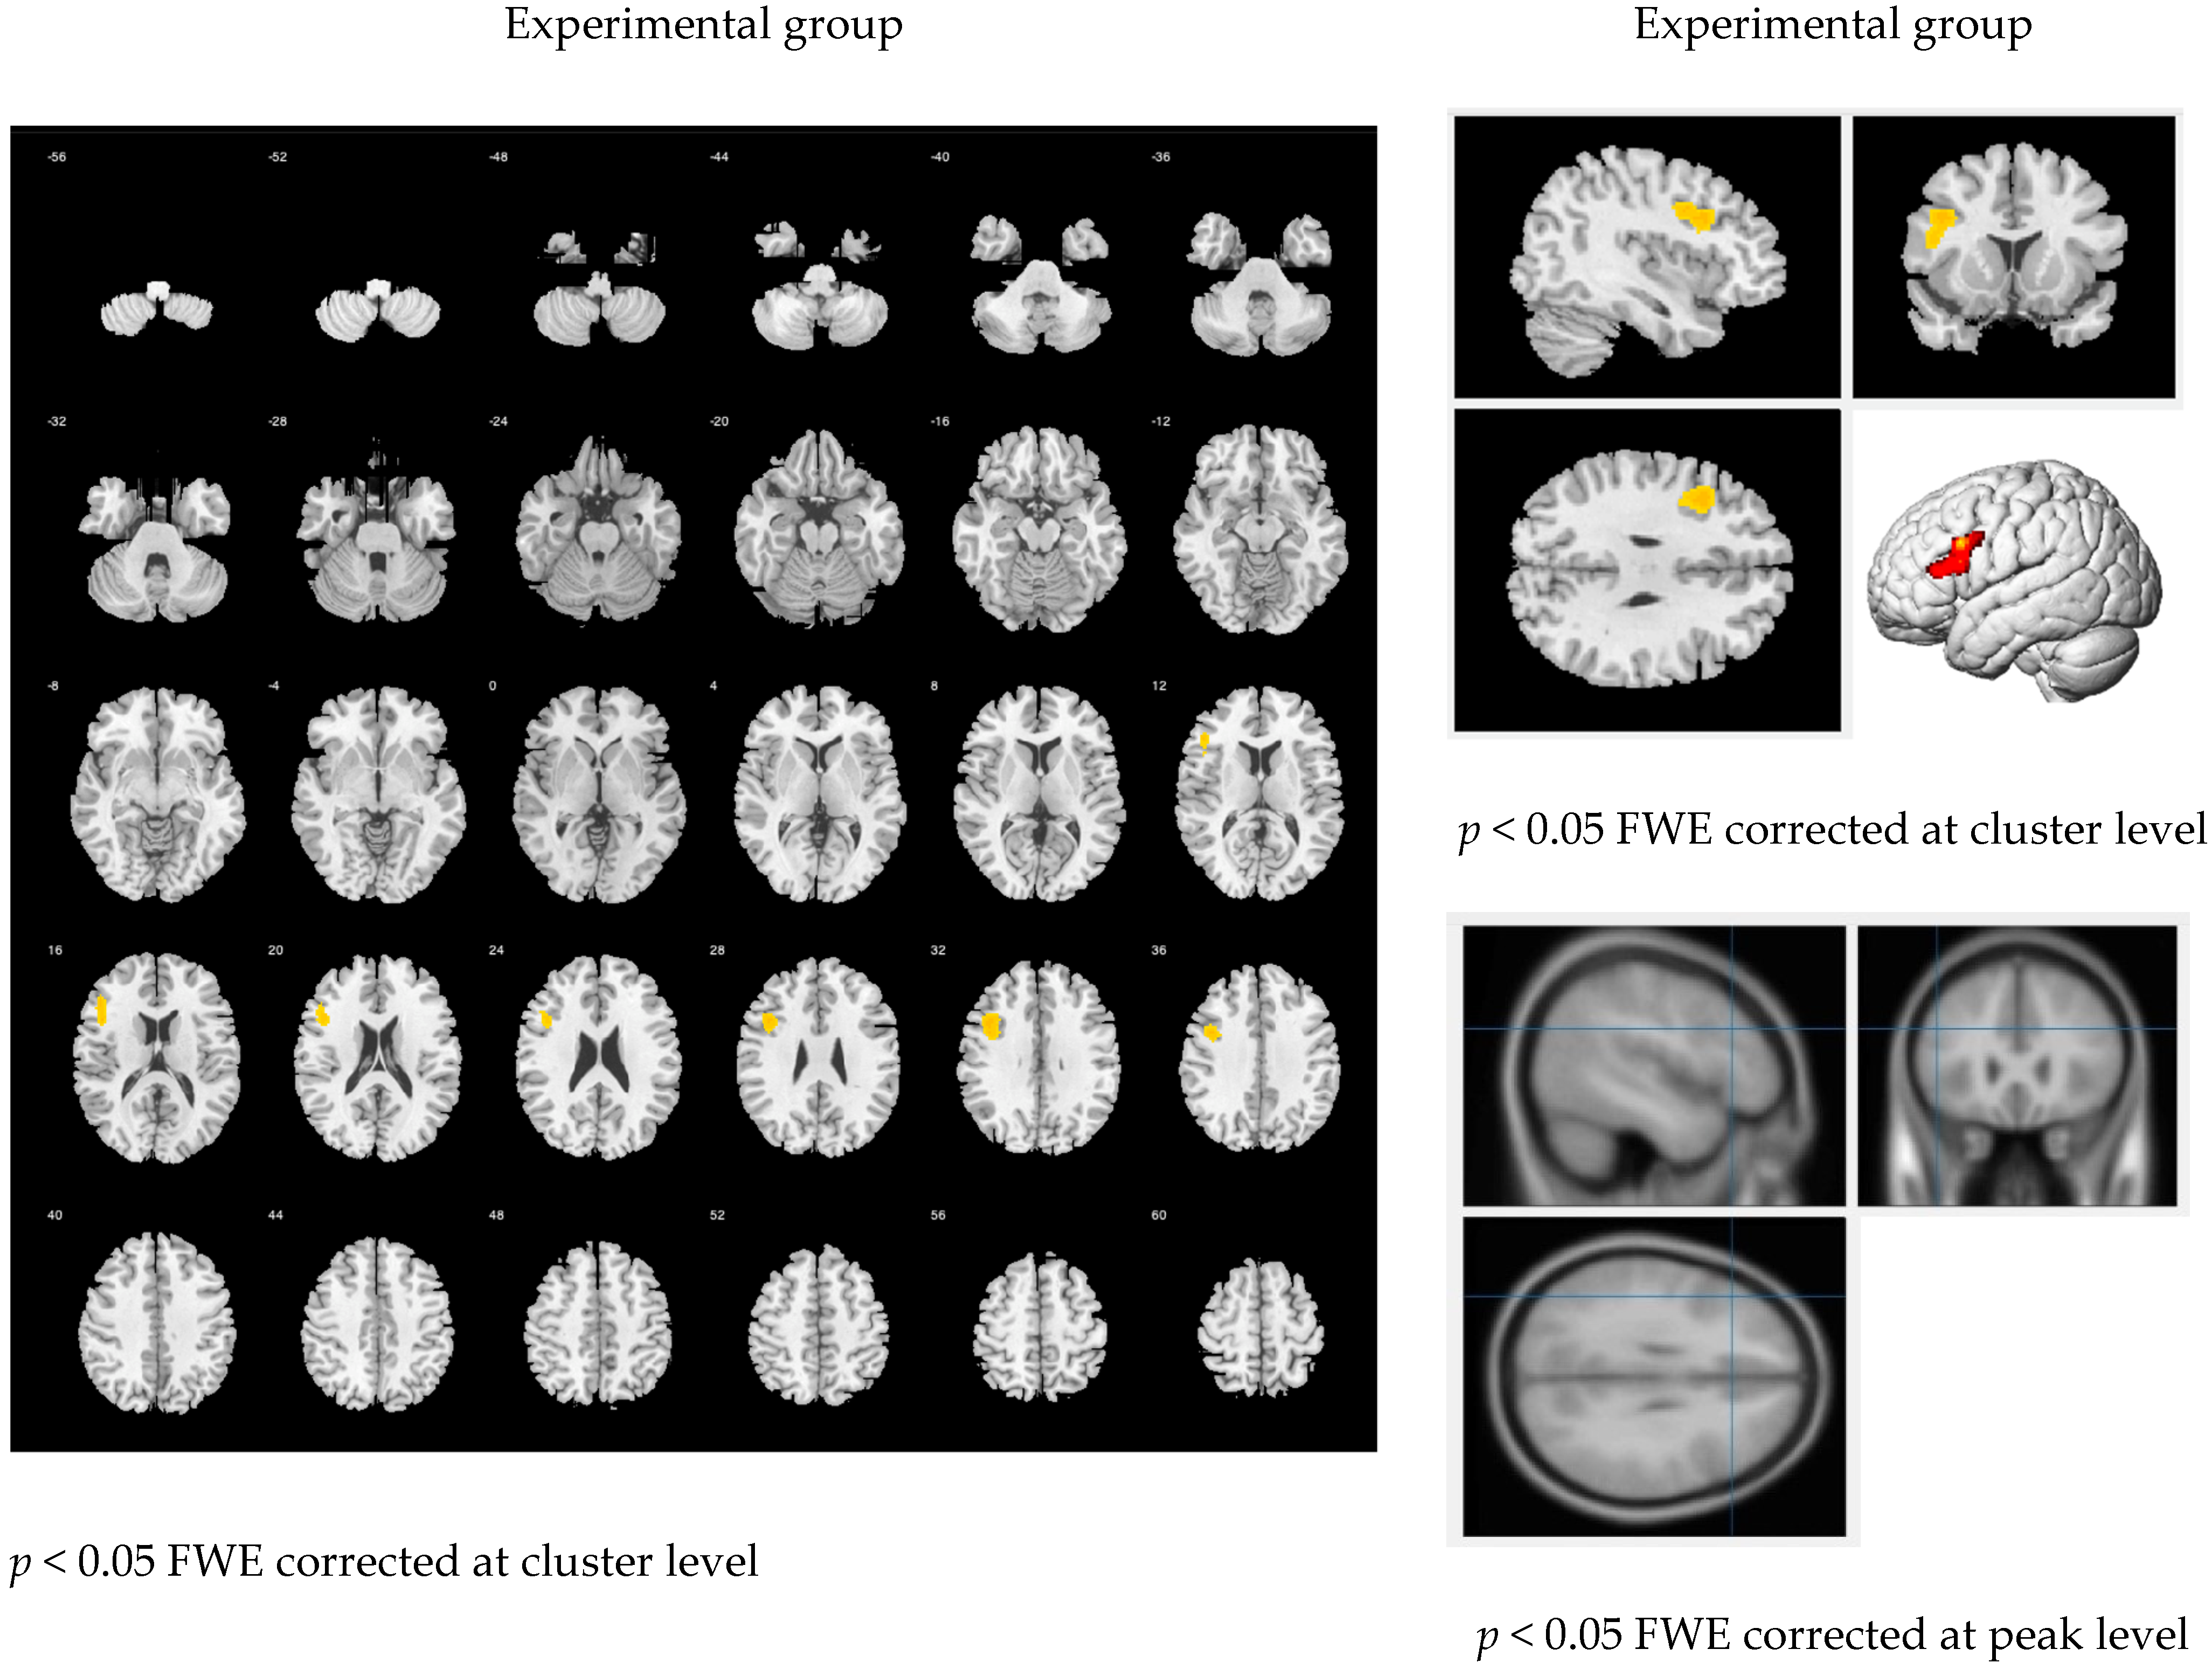

3.2. Brain Images

3.2.1. The Main Effect of the Handwriting Tasks

3.2.2. The Language Effects among Different Tasks

3.2.3. Learning Effects through Scaffolding Instruction

4. Discussion

4.2. Brain Images